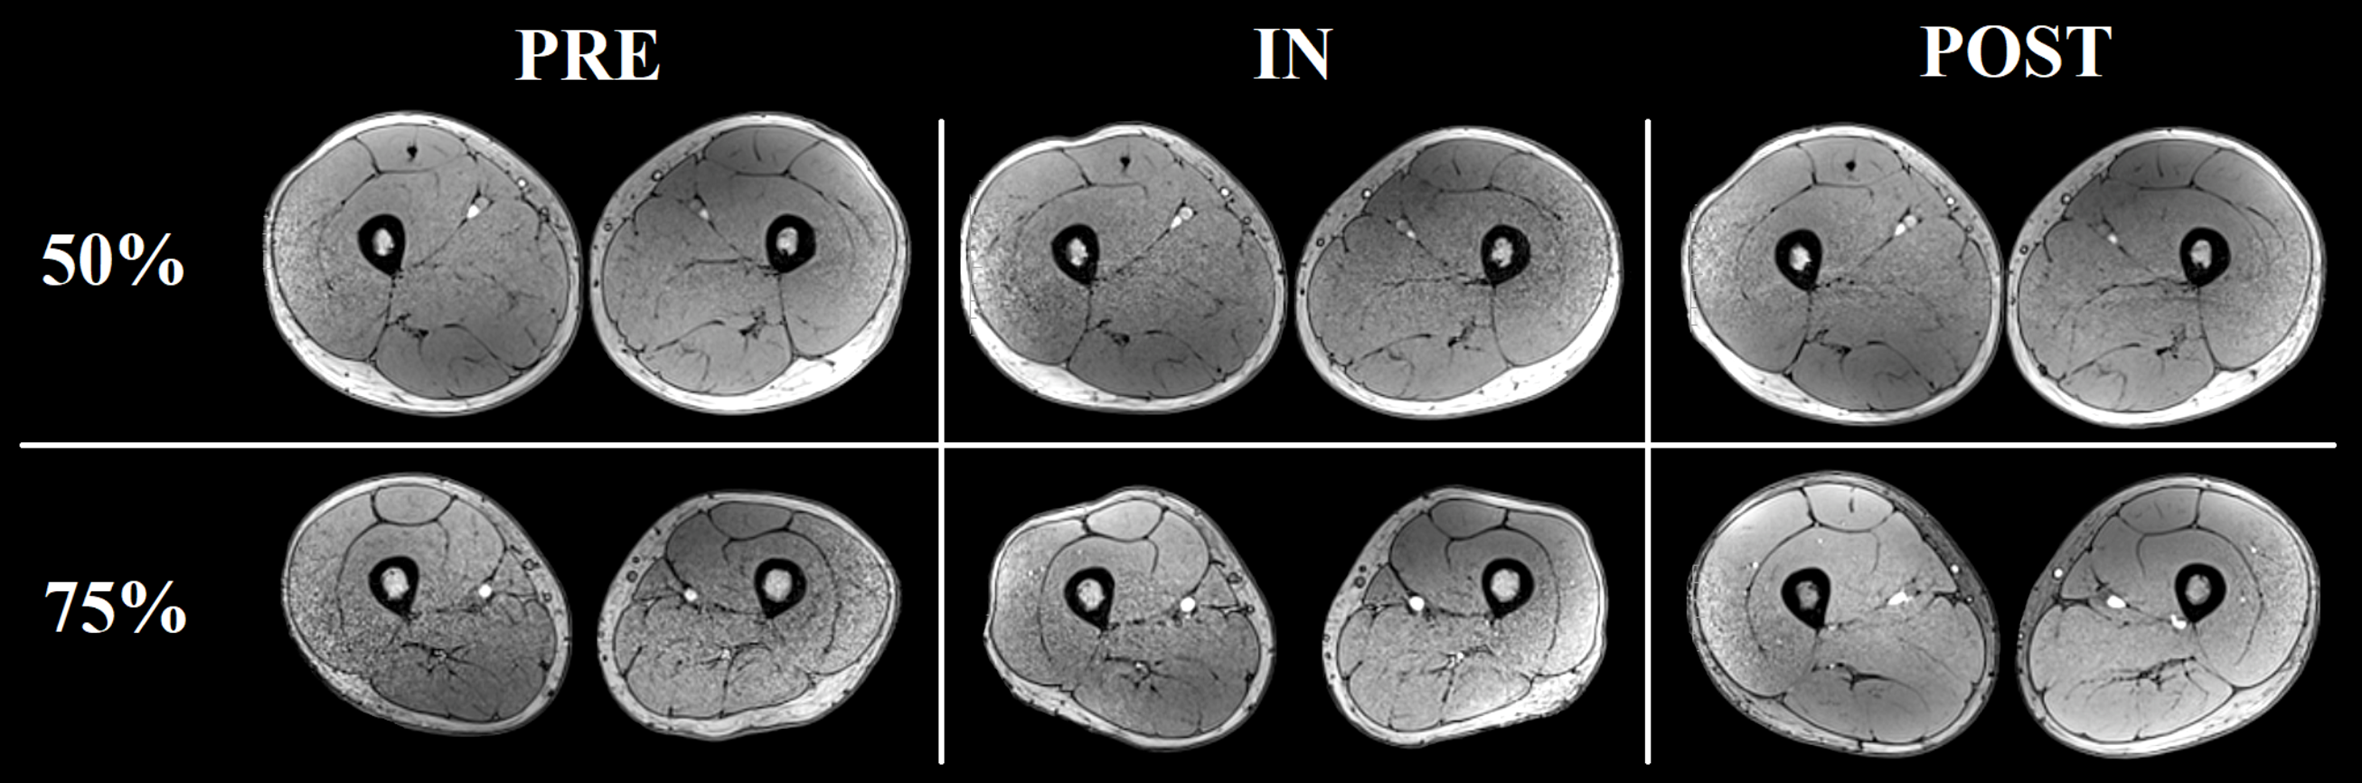

There was a significant main effect of time for all the muscles analyzed, except for SM (Table 1). Significant increases in RF, VM, VL+VI, ADD, and BFL volume were detected from PRE to IN and from PRE to POST (all P < 0.05). A representative case is shown in Figure 7.

FIGURE 7. Representative increases in thigh muscles CSA (at ≈ 50% and ≈ 75% the length of the femur) as assessed by consecutive MRI scans before (PRE), and after 5 (IN) and 10 (POST) training sessions from one of the volunteers.